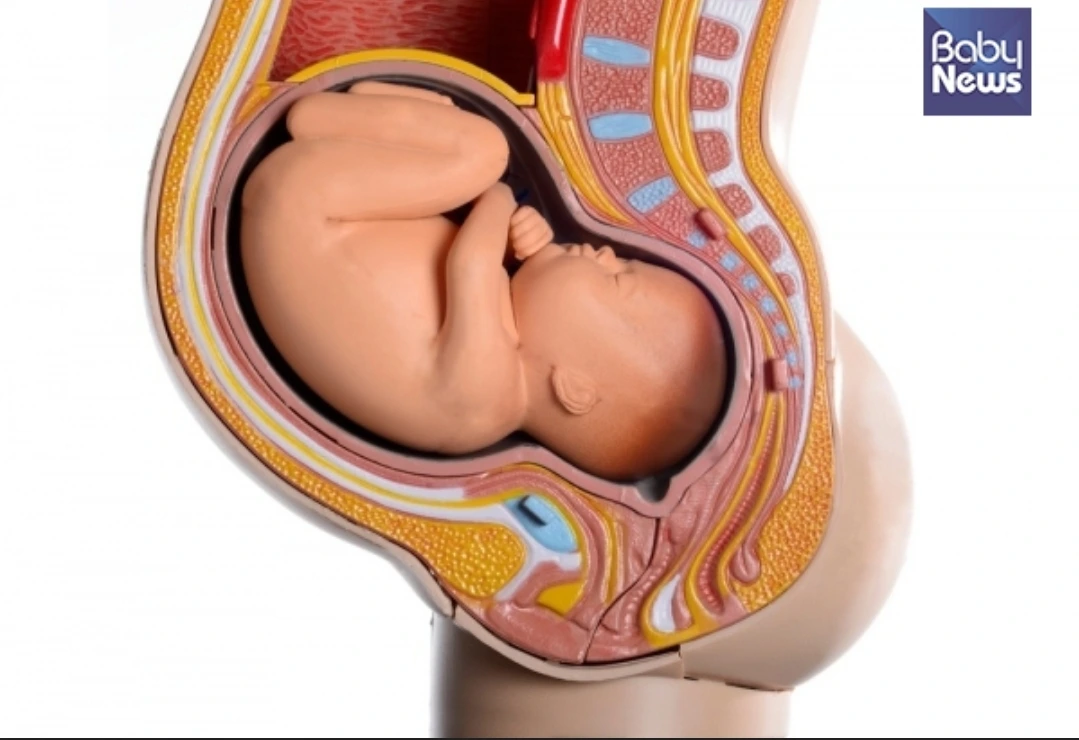

정상위

진통이 없으면 북극곰 자세를 했다가 진통이 있으면 편안한 자세를 하고. 그래도 아가가 정상위가 안돼서 간호사분이 억지로 자세를 돌렸어. 보통 정상위가 안되면 제왕절개를 하는 경우가 많다고 하는데 엄마는 그래도 잘 이겨 냈더라. 제왕절개가 회복이 더디다는 점이 있어서 자연분만을 하고 싶어 했거든.